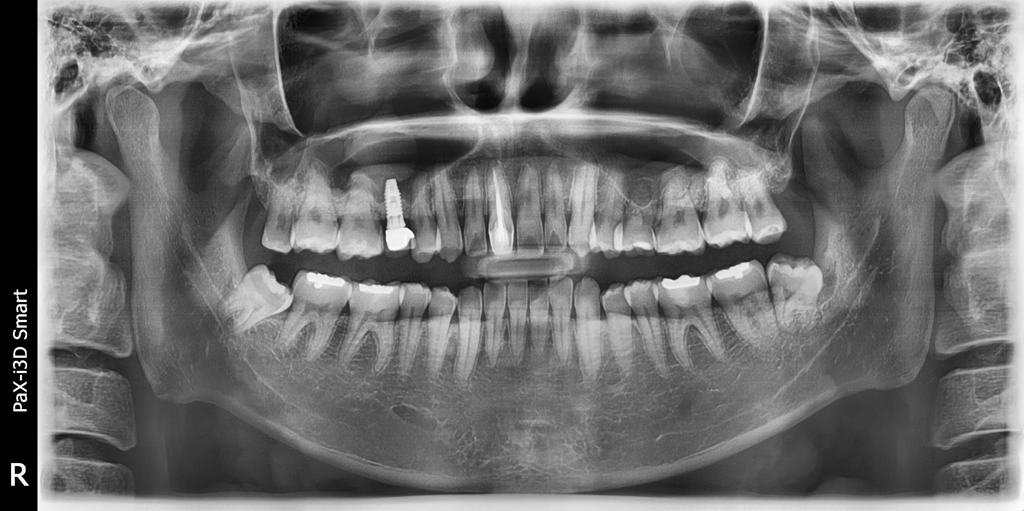

임플란트가 있는데요 치아교정 가능한가요?

오른쪽 상악에 임플란트를 했는데

부분교정이라도 가능할까요?..

비발치로 , 임플란트는 손안대고 하고싶은데ㅣ...

• 1번 째 사진